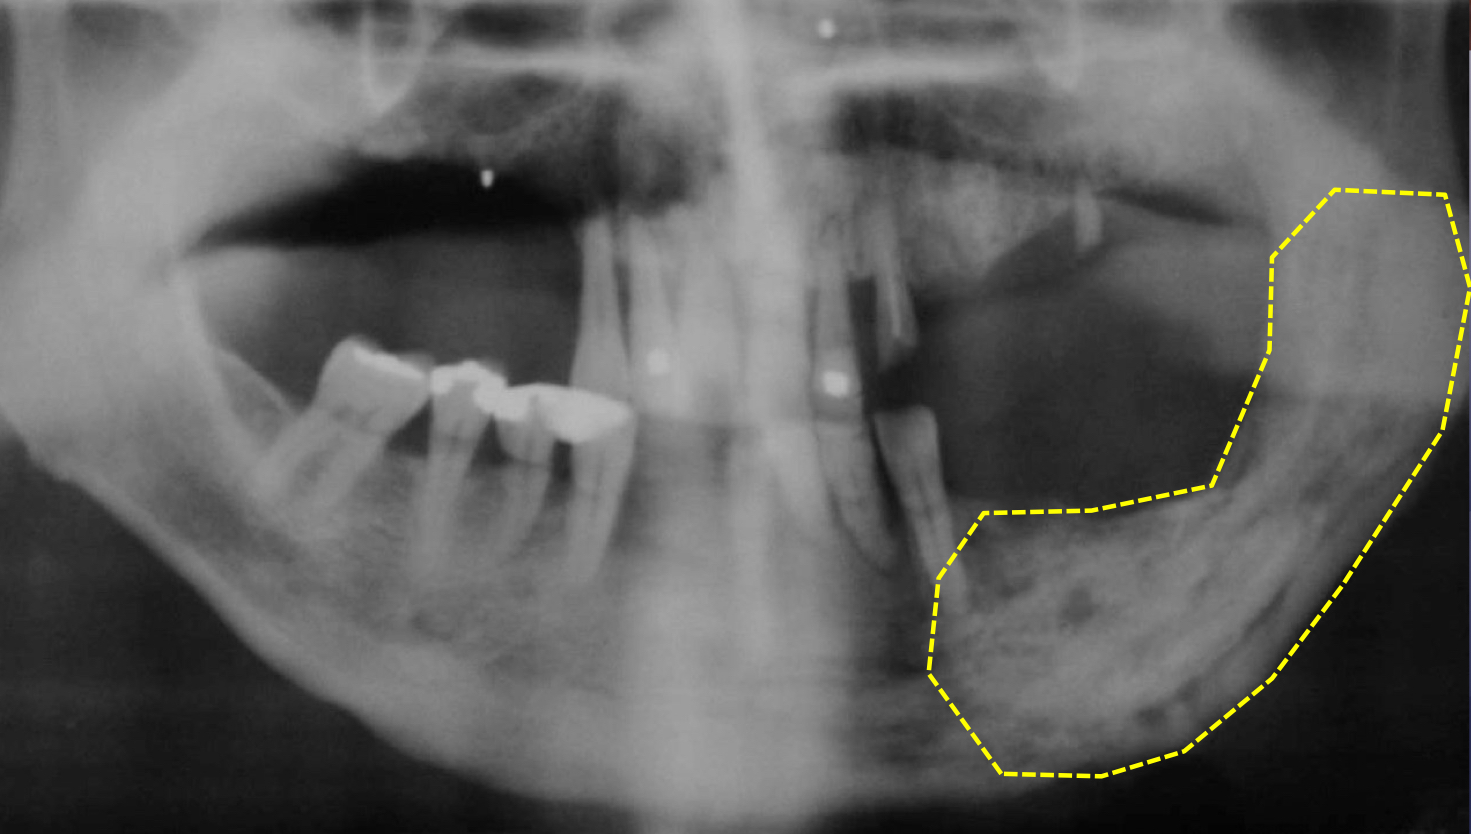

which osteomyelitis phase?

periphery:

poorly defined

non-corticated

gradual transition to normal trabeculae

acute

internal structure:

decrease in bone density, loss of sharpness of trabeculae

localized or scattered regions of radiolucency, ill defined periphery

mixed radiolucent-radiopaque areas

“moth-eaten”

irregular outline

help: mandibular trabeculae looks like lasagna but here more granular and indistinct

moth bitten acute osteomyelitis

sequestration, sinus tract or fracture

white and black arrow

some effects on surrounding structures:

bone formation, periosteal stimulation = onion skin

bone resorption

periosteal reaction

new bone formation parallel to the cortex (almost looks like periosteum lifted and bone under)